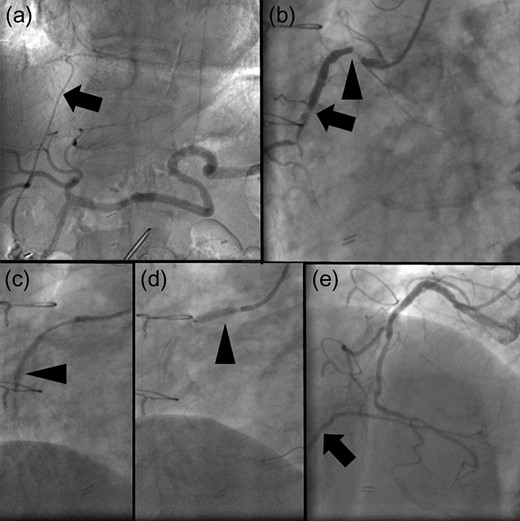

The patient underwent coronary arteriography preoperatively. Based on confirmation of a patent RGEA (Fig. 1a), the stenotic native coronary artery was revascularized (Fig. 1b) using bare-metal stents (BMS) to avoid cardiac ischemia due to intraoperative manipulation of the RGEA (Fig. 1c–e). Definitive gastric surgery was performed 4 weeks after revascularization. The location of the RGEA was easily confirmed intraoperatively (Fig. 2a). Indigo carmine dye was administered into the greater curvature of the gastric angle, adjacent to the tumor, to observe the lymph stream, through which the infrapyloric lymph ducts could also be observed (Fig. 2b). We detached the adipose tissue bearing lymphatic tissue along the outermost layer of nerves that twine around the surface of the pancreas and anterior superior pancreaticoduodenal vein [7] (Fig. 2c). After the lymphatic tissue was removed along the outermost layer of nerves, the remaining skeletonized RGEA was preserved (Fig. 2d). Histopathologically, the tumor was 35 × 25 mm2, type 3, por2, pT3, pN0. Heparin treatment was initiated on postoperative day (POD) 1. However, it was interrupted from PODs 6 to 13 because of a transient hematic discharge from the drainage tube, and antiplatelet therapy was reinitiated on POD 15. The patient was discharged on POD 18. Over the 41-month follow-up period, he did not experience any recurrence of the gastric cancer or cardiac ischemia.

(a) Angiogram of the celiac artery showing a patent right gastroepiploic artery (RGEA) (arrow). (b) Coronary angiogram showing severe stenosis of the native right coronary artery (RCA). The proximal and middle portions of the RGEA exhibit 99% (arrowhead) and 90% (arrow) stenosis. (c, d) Two bare-metal stents (BMS) are implanted in the native RCA (arrowheads). (e) When the RCA is revascularized using the BMS, the restricted blood flow improved. Moreover, the retrograde flow of contrast medium to the patent RGEA is observed (arrow).